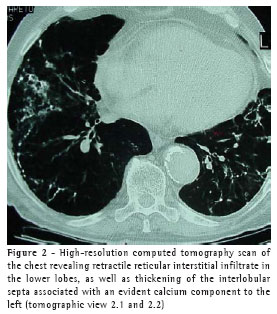

A high-resolution computed tomography scan of the chest (Figure 2) revealed the presence of retractile reticular interstitial infiltrate in the lower lobes, as well as thickening of the interlobular septa accompanied by an evident calcium component to the left, centrilobular emphysema in the upper lobes, left pleural thickening, an aorta affected by ectasia/atheromatosis, and normal cardiac region.